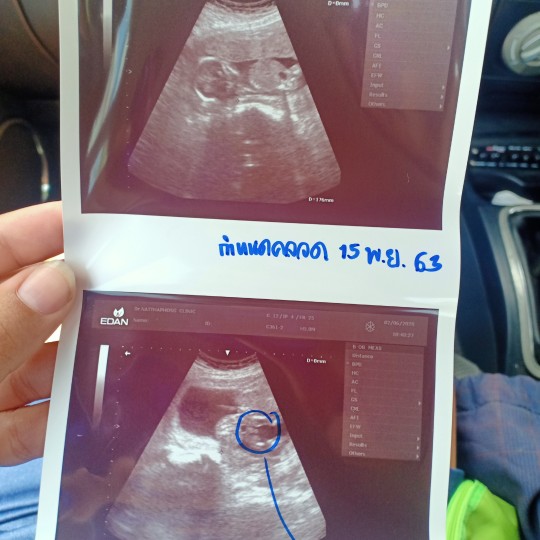

15 พฤจิค่า ผู้ชาย 👶🏻